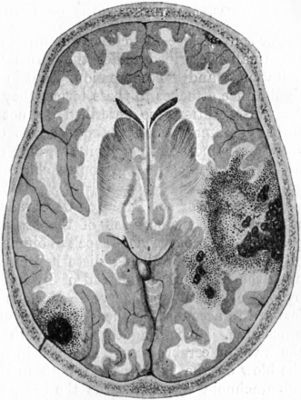

| 184. | Contusion and Laceration of Brain | 343 |

| 192. | Diagram of Extra-Dural Abscess | 374 |

| 195. | Diagram illustrating sequence of Paralysis, caused by Abscess in Temporal Lobe | 380 |